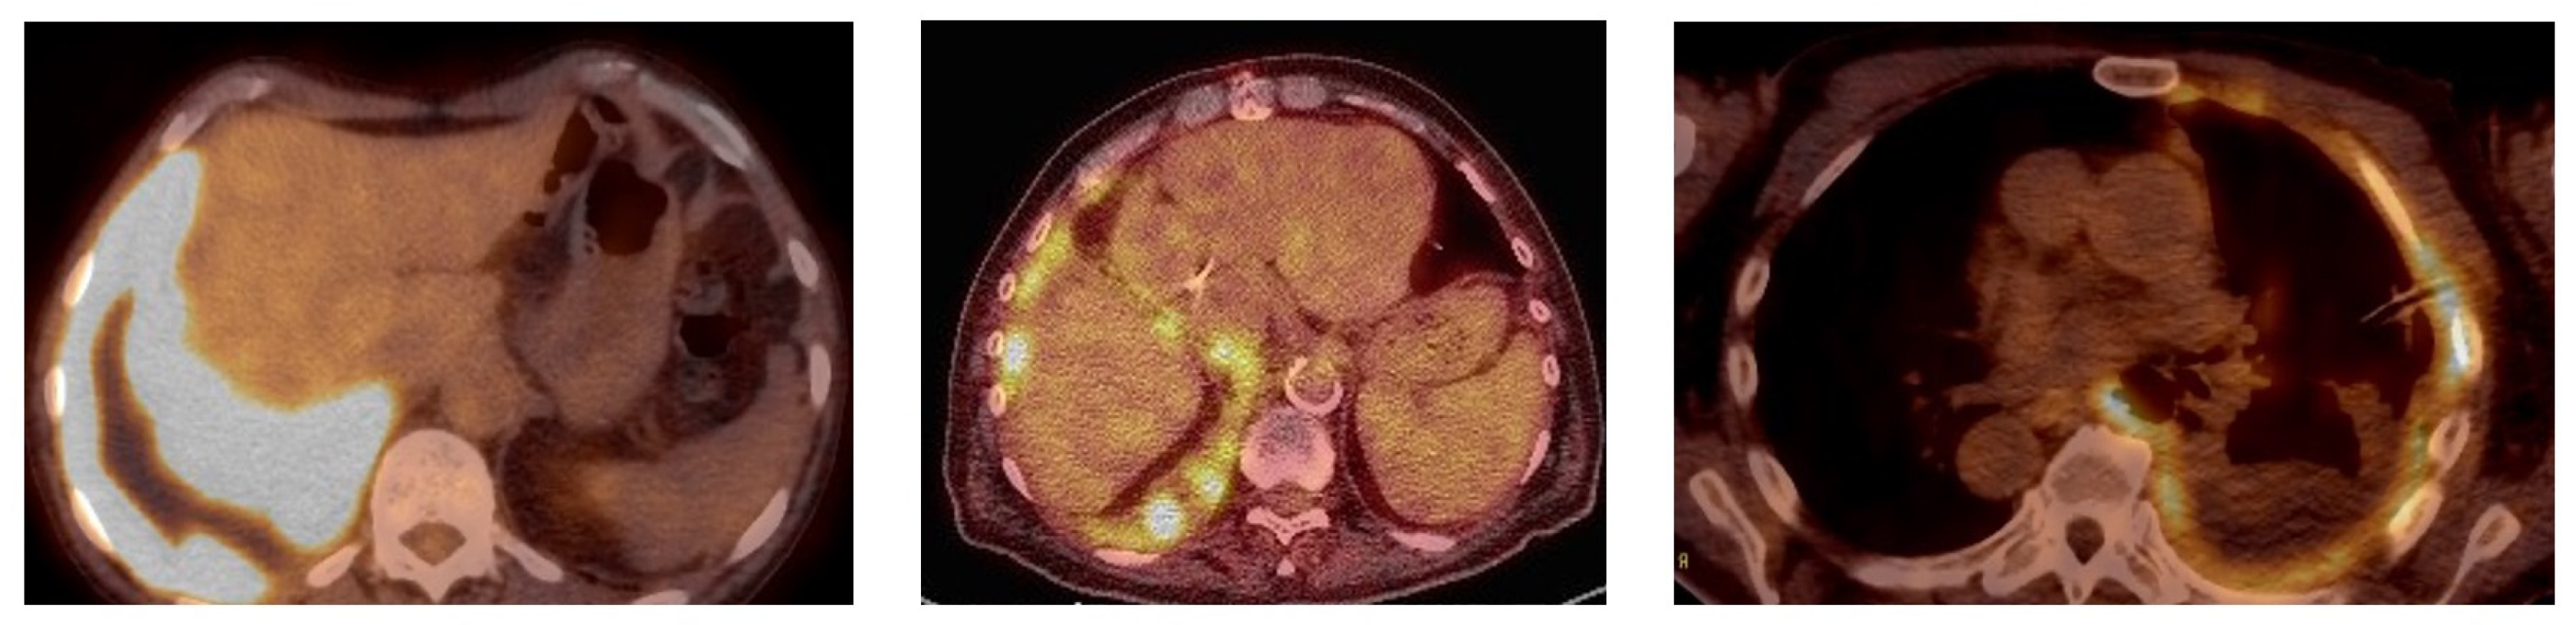

Two physicians blind to the results of the pleural cytopathology reviewed the uptake pattern of the FDG-PET studies. A third physician independently evaluated imaging and adjudicated the results in the event of discordance of interpretation. If FDG uptake was identified, it was characterized as having a linear, a nodular or an encasement pattern (Figure 1). The descriptions are self-explanatory, but there were cases where multiple patterns of uptake were present in the same patient. This was most commonly seen in patients with pleural nodules and the involvement of pleural lining, which is visually seen as the linear uptake. Each pattern of uptake was tabulated separately, even if present in the same patients. However, the abnormality was characterized as having an encasement pattern in patients for whom the FDG-PET uptake represented the involvement of the vast majority of the pleural surface, with the abnormal uptake appearing to wrap around the lung. This encasement pattern could have linear and nodular areas but was labeled as encasement given the overwhelming extent of involvement. While some patients had both patterns of nodular and linear uptake, encasement represented a more advanced degree of involvement and was mutually exclusive with nodular and linear uptake. The FDG-PET results were compared to the pleural cytopathology to assess the utility of this imaging modality for the confirmation of MPE.

Figure 1. FDG-PET uptake patterns: (left panel) is encasement, (middle panel) is nodular and (right panel) is linear.

Some cancers such as malignant mesothelioma are more likely to have pleural involvement, and FDG-PET seems especially useful in these cases [23,24]. Most of the cases of mesothelioma had an encasement pattern. However, it should be noted that of the 20 patients with an encasement pattern, the majority (60%) had a non-mesothelioma diagnosis. Except for one patient, primary lung cancer was the other malignancy most often associated with encasement on FDG-PET scans. This pattern of encasement and increased FDG-PET uptake was felt to be essentially pathognomonic for malignancy. While a common pattern in mesothelioma, other malignancies can present with a similar pattern of FDG-PET uptake. Encasement had a 100% positive predictive value for MPE. Conversely, encasement was the only FDG-PET pattern that was not seen in those patients with negative pleural fluid cytology. In those with a MPE, the absence of encasement virtually excluded malignant mesothelioma as the diagnosis with a NPV of 94.6%. The pattern of FDG-PET uptake may also be especially helpful in identifying MPE. Focusing on patients with pleural FDG-PET uptake, about 90% with either nodular or linear uptake were eventually identified as having MPE. The patterns of update generally involved an extensive portion of pleural surface, as depicted in the figure, and were typically adjacent to pleural effusions, as well as infrequently juxtaposed to areas of abnormal lung parenchyma.